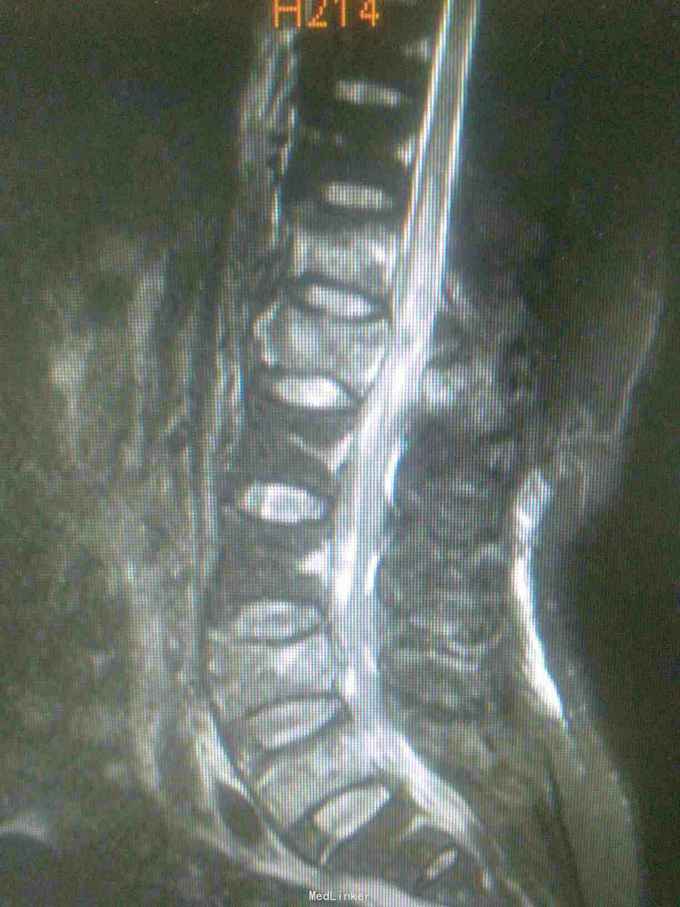

诊断腰1,腰4椎体爆裂性骨折,腰5椎体压缩性骨折,脊髓圆锥损伤双下肢截瘫。患者入院后48小时内行了腰椎后路腰1.4椎体切开复位椎弓根钉内固定,腰1椎板切除,椎管扩大成形,横突间植骨融合术。

1.大家看看这个钉棒打得怎么样,欢迎拍砖,2.由于我院因材料没的问题有,急诊手术能力,影响脊髓损伤病人的手术疗效,,在没有内固定的前提下,一期先减压,二期上内固定,效果怎么样,请同行前辈多指导。